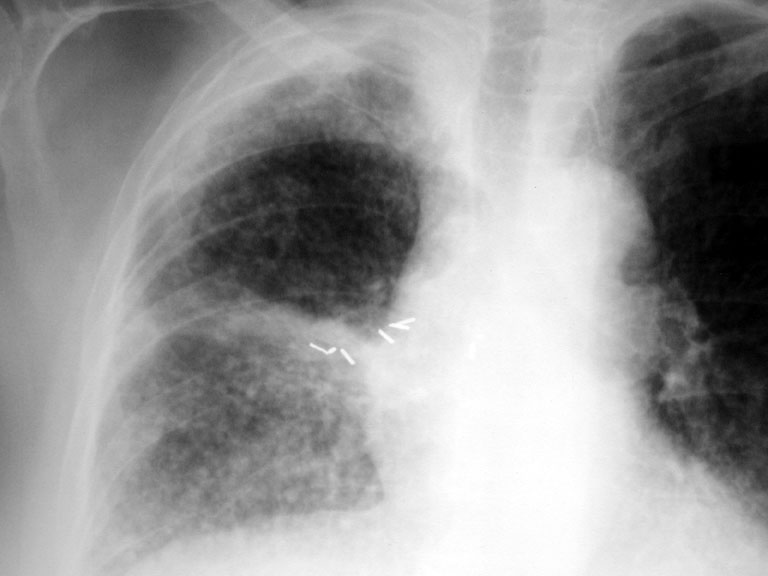

• Progression to multicentric acinar nodules

Multi centric alveolar nodules